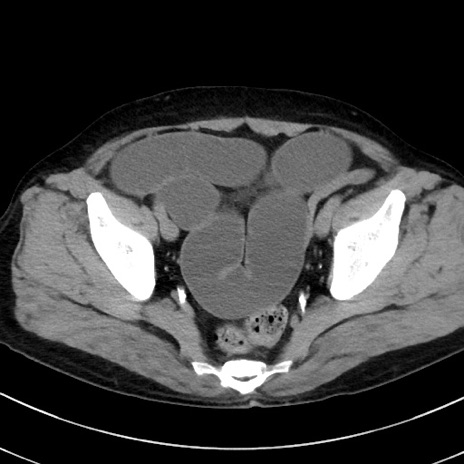

冠状断像

症例38(横断像)

【症例】70歳代 男性

【主訴】腹痛・嘔吐

【現病歴】昨晩より、嘔吐・腹痛あり。今朝になっても嘔吐あり。来院。

【既往歴】心臓バイパス手術、開腹胆摘、腸閉塞

【身体所見】BP 107/71mmHg、HR 116/min、腹部:平坦、軟、下腹部に軽度圧痛あり。反跳痛なし。

【データ】WBC 15100、CRP 0.32